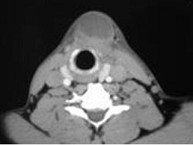

8.患者腫塊圖像及影像學檢查結果見下圖,本患者應考慮為  (    )

正確答案:8.A;9.A